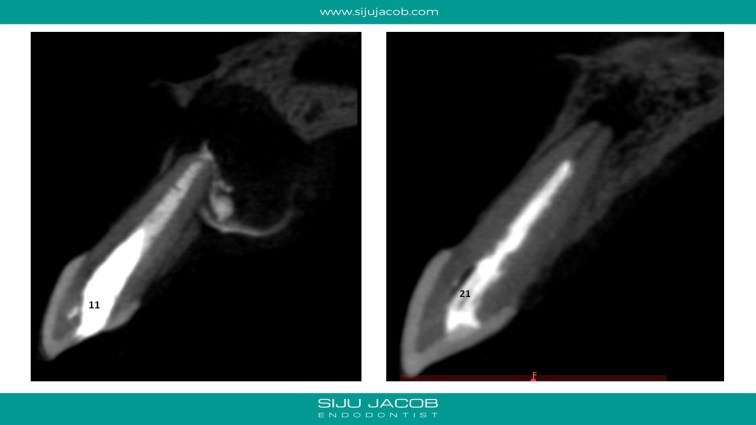

This patient had a large lesion in the right maxillary anterior region. The lateral Incisor tested vital. I decided to re-treat only the central Incisor. Despite several calcium hydroxide changes spread over 2 months, there was persistent drainage of pus. Instead of opting for the more radical option of endo on the lateral and immediate surgery, we decided to do decompression. The drainage stopped and the tooth was subsequently obturated. Patient recently came for some other work and I took a 5-year recall raiograph. It seems to be holding on for now. I was tempted to do the endo on the lateral on several occasions, but it always tests vital.